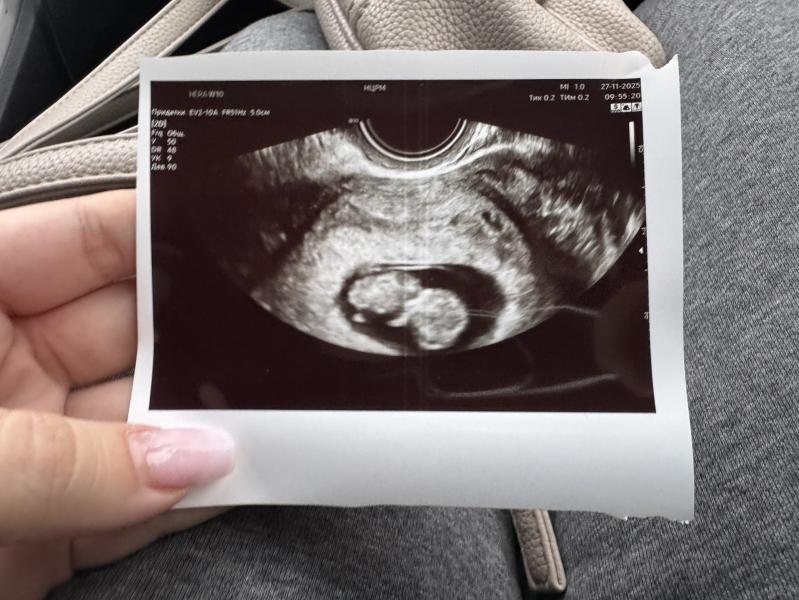

Первые шевеления малыша на УЗИ в 10 недель беременности

А человек растёт. Человек ручкой помахал на узи:)

10нед

27.11.2025